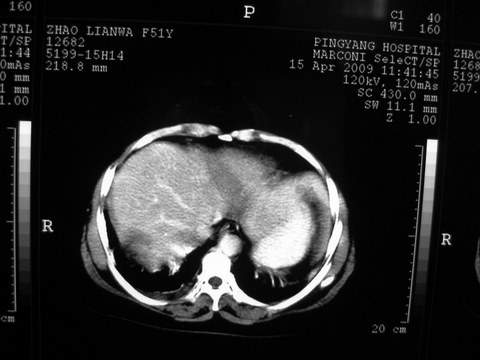

标题: CT19402:肝脏巨大囊实性占位 [打印本页]

标题: CT19402:肝脏巨大囊实性占位

患者 女 51岁 两天前感觉上腹疼,无明显诱因,b超示肝右叶囊实性占位,边缘清楚,其内回声不均匀,ct增强如图,大家看看是什么 ,病人一年前及两月前b超检查只是提示胆囊炎

外院术后,证实肝癌合并出血

特点:1,病灶发展迅速,(2月前正常)[br] 2,囊实性,且并边界清晰光滑,呈右后叶赘生性。囊性区无强化,实性部分较多轻度强化,边界欠清。考虑囊腺癌或囊腺瘤。

出病理 中分化肝细胞癌合并出血